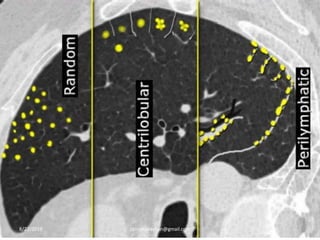

Nodular Pattern :

Three categories: according to their distribution

A. Random

B. Centrilobular

C. Perilymphatic

Random distribution:

-Random refers to no preference for a specific location

in the secondary lobule.

-Nodules are randomly distributed relative to

structures of the lung and secondary lobule.

-Nodules can usually be seen to involve the pleural

surfaces and fissures, but lack the subpleural

predominance.8/27/2019 zannatulrayhan@gmail.com

Centrilobular distribution:

-nodules are limited to the centrilobular region.

-centrilobular nodules spare the pleural surfaces.

-most peripheral nodules are centered 5-10 mm from

fissures or the pleural surface.

Perilymphatic distribution:

- nodules are seen in relation to pleural surfaces,

interlobular septa and the peribronchovascular

interstitium.

-Nodules are almost always visible in a subpleural

location, particularly in relation to the fissures.

8/27/2019 zannatulrayhan@gmail.com

NODULAR PATTERN8/27/2019 zannatulrayhan@gmail.com